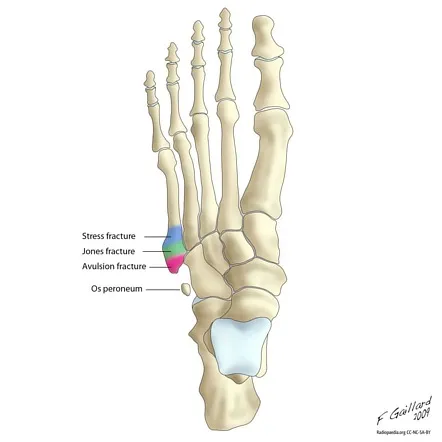

Een Jones fractuur is een breuk van het vijfde middenvoetsbeentje, het lange bot aan de buitenzijde van de voet dat naar de kleine teen leidt. Het is een specifiek type breuk, gelegen op de overgang tussen de basis en het midden van dit bot. Dit gebeurt meestal indirect, bijvoorbeeld wanneer je door een misstap jouw voet gebroken hebt, of wanneer je tijdens het sporten plotseling op de buitenkant van de voet landt. Deze breuk onderscheidt zich van andere voetbreuken doordat de genezing trager verloopt door de mindere bloedtoevoer in dit gebied.

3. Beeldvorming:Op een röntgenfoto van de voet is een Jones fractuur meestal duidelijk zichtbaar als een breuklijn in het vijfde middenvoetsbeen. Het is belangrijk om de Jones fractuur op beeldvorming te onderscheiden van een pseudojones fractuur (avulsiefractuur) aangezien de behandeling anders verloopt. Bij twijfel, of om de mate van verplaatsing beter te beoordelen, kan aanvullend een CT-scan uitgevoerd worden.